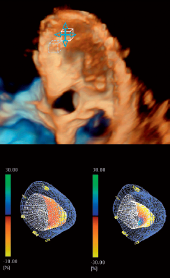

Технология 3D Wall Motion Tracking - сердце, объемная трехмерная (3D) структура, а значит и движение сердца и смещение спекл- шумов происходит в трёх плоскостях.

3D-технологии используются для получения полного объема данных о структурном и функциональном состоянии левого желудочка. Чтобы рассчитать движение стенки в трех измерениях, требуется хорошо сбалансированный набор данных с точки зрения пространственного и временного разрешения.